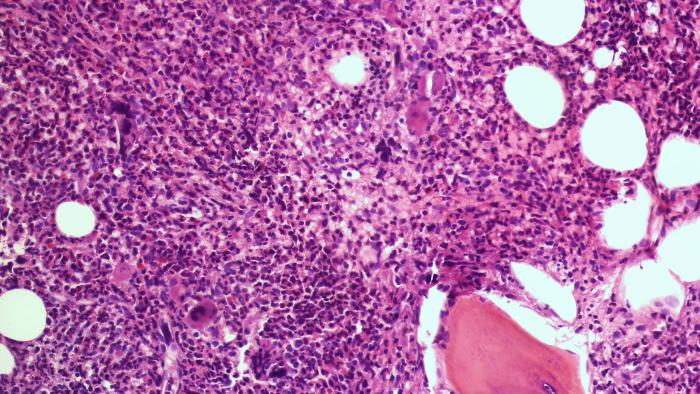

D’acord amb l’anàlisi i la previsió que recull la darrera actualització del Pla de salut de Catalunya i del Pla director d’oncologia, és necessari dur a terme accions prioritàries en el camp de la malaltia oncològica en el nostre país. L’Hospital Universitari Vall d’Hebron està especialment dotat per afrontar un Pla d’atenció oncològica integral, en què els serveis treballin de manera coordinada. Això és possible per la presència d’uns serveis especialitzats com ara el d’Oncologia Mèdica, Oncologia Radioteràpica, Hematologia Clínica, especialitats quirúrgiques, especialitats mèdiques, Infermeria especialitzada, Anatomia Patològica, Serveis de Diagnòstic per la Imatge i Atenció Primària. L’expertesa professional i la capacitat de treball en comú són la base per acomplir aquesta missió.